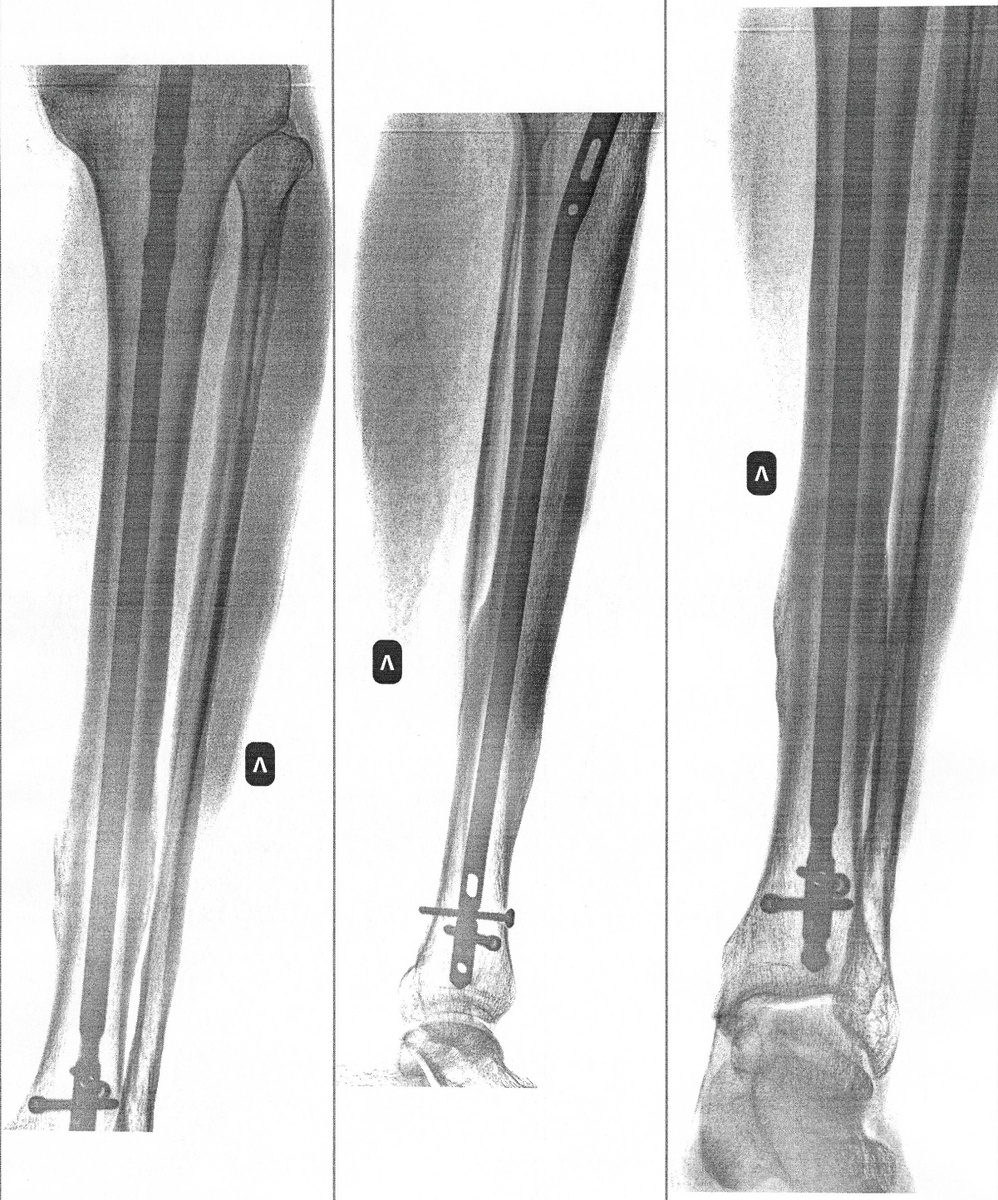

Рентген перед операцией. Видны места сросшихся переломов.

Утром вторника сделали укол антибиотика, а около 12 часов забрали в операционную. Операция заняла около получаса. Мне выкрутили оставшиеся два фиксирующих шурупа, сделали разрез под коленом, вскрыли кость и удалили штифт, вставив в него специальное приспособление. По словам доктора, штифт вышел достаточно легко. Бывает, что кость после сращивания зажимает его в канале. Так же (это я узнал из ю-туба) существуют штифты отечественного и импортного производства, и приспособления для их удаления так же разные. Наверное, это связано с разной формой захвата. Я заранее уточнил у доктора, все ли у них есть приспособления, потому что видел сюжет, где человеку удалили шурупы, а для штифта не нашлось подходящего съемника (ужас!).